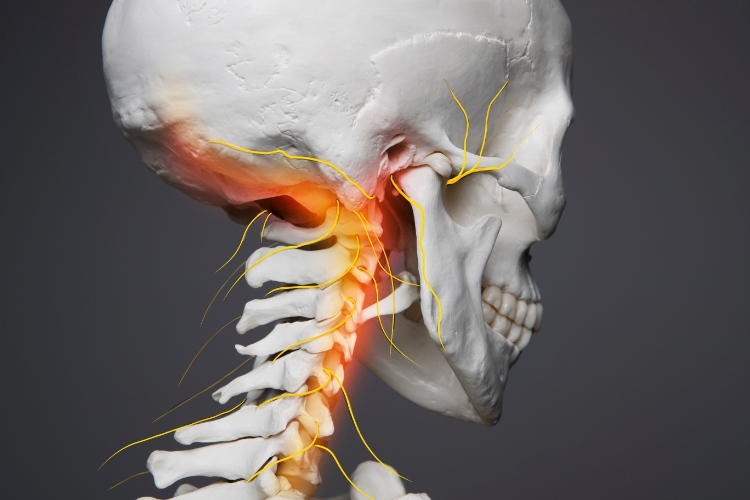

ვერტებრო-ბაზილარული უკმარისობა (VBI) არის მდგომარეობა, რომელიც გამოწვეულია თავის ტვინის უკანა ნაწილის არასაკმარისი სისხლით მომარაგებით. ეს უკანა ნაწილი მოიცავს თავის ტვინის უკანა წილს, ტვინის ღეროსა და ნათხემს, რომლებიც პასუხისმგებელია ისეთ მნიშვნელოვან ფუნქციებზე, როგორიცაა მხედველობა, წონასწორობა, კოორდინაცია და სასიცოცხლო ფუნქციები (სუნთქვა, გულისცემა). სისხლის მიწოდებას ამ ზონებში უზრუნველყოფს ორი ხერხემლის არტერია (vertebral arteries), რომლებიც ერთიანდებიან ბაზილარულ არტერიაში (basilar artery) და ქმნიან ვერტებრო-ბაზილარულ სისტემას.

- სპონდილოზი (კისრის მალების ოსტეოართროზი): კისრის მალების დეგენერაციულმა ცვლილებებმა შეიძლება გამოიწვიოს ხერხემლის არტერიების კომპრესია, განსაკუთრებით თავის მობრუნების დროს.

სიმპტომები ხშირად ძლიერდება თავის მობრუნების ან გადაწევის დროს.

- კისრისთვის საზიანო მოძრაობების თავიდან აცილება: მოერიდეთ მკვეთრ და უეცარ მოძრაობებს კისრის არეში, ხანგრძლივად ერთ პოზიციაში ყოფნას, განსაკუთრებით თავის გადაწევას ან მობრუნებას.